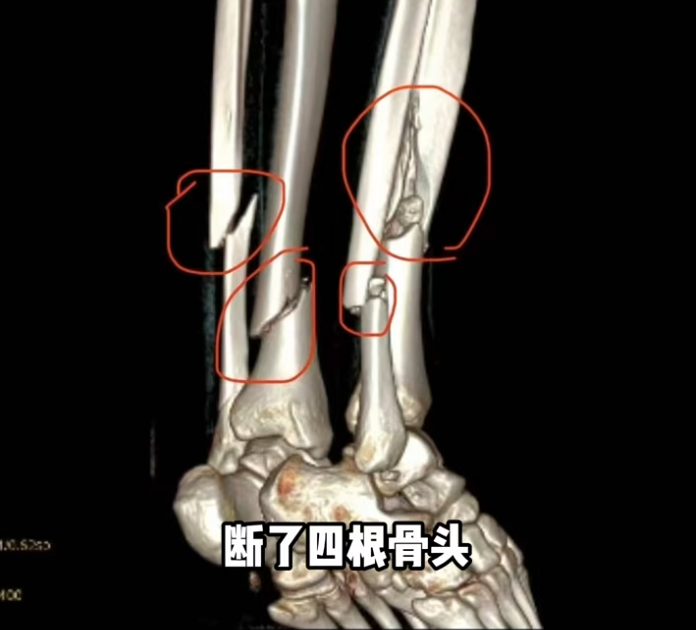

据她2月27日发布的动态,她在新疆滑雪时摔倒,断了4根骨头,右腿胫骨粉碎性骨折,处理伤口的时候,她痛苦喊叫声响彻诊室。

据她描述,轻微的活动都能感受到碎骨扎进肉里,不敢想象有多疼。千一称在新疆接受手术,左腿2块钢板16颗钉子,右腿2条髓内钉和6颗固定钉子,缝了45针。麻醉药效过去后,剧痛和反复发烧都在折磨她,甚至开始说胡话、记忆混乱的症状。3月8日,她发文报平安,称自己状态好多了,并在视频中表示,明年再战。网友们纷纷提醒,如此严重的伤势,不能马上从事剧烈运动的。小丽星骑不快的鸡腿儿:但愿这个不是剧本,这个踝关节面估计已经创伤性关节炎了,手术做完只是开始,后面的康复和后遗症会终生痛苦。量体裁衣:你开心的日子就是这几天,以后康复后遗症有你哭的,我就是一个小骨折康复以后都有一点轻微后遗症。Sophia:明年也战不了,拆钢板还得养一年。我就是,两年没滑雪了,甚至跑步医生都不让。